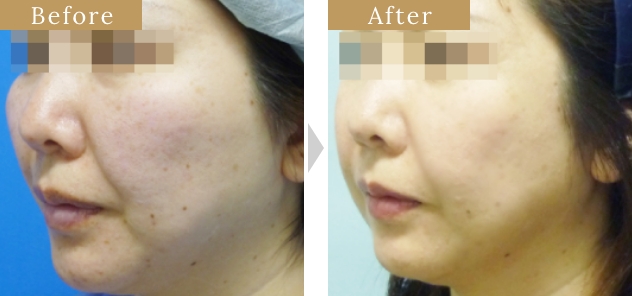

症例